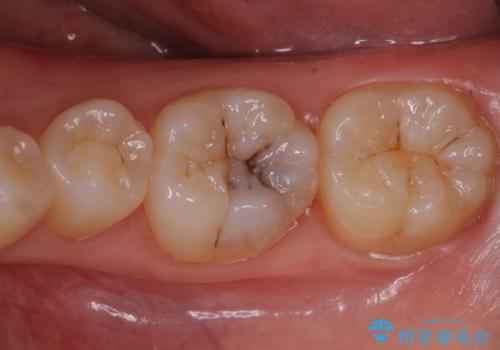

また、一つ手前の歯に小さな虫歯があったため

e-maxインレーでの治療を行いました。

銀の詰め物を拡大鏡下で取り除き、う蝕がないことを確認してから

ZrCrの被せ物で治療を行いました。